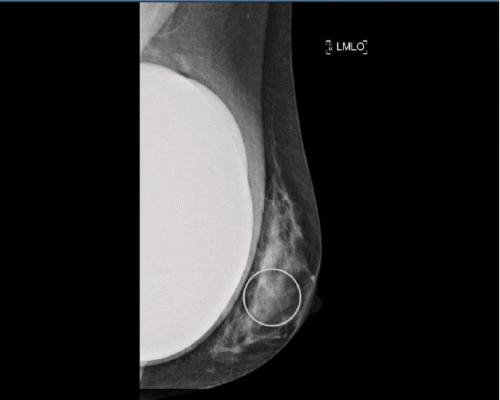

Intraoperatively, a significant amount of straw-colored free fluid was found within the peritoneal cavity, along with scant blood-tinged fluid in the pelvis. Approximately two feet proximal to the ileocecal junction, a Meckel’s diverticulum (MD) was identified on the antimesenteric border of the ileum (Figure 1). The mechanical obstruction was caused by an adhesive band originating from the gastrocolic omentum, which had encircled the Meckel’s diverticulum, leading to a secondary mesenteric volvulus of the involved bowel segment.

Figure 1. Intraoperative Identification of Meckel's Diverticulum. Published with Permission.

Given the patient’s advanced age, overall frailty, and the absence of gross inflammation or ischemia of the diverticulum itself or adjacent bowel, a decision was made to perform a diverticulectomy rather than a segmental bowel resection. The broad-based morphology of the diverticulum was deemed amenable to complete excision using a stapling device without compromising the luminal diameter of the distal ileum. The omental adhesive band was incised, and the Meckel’s diverticulum was detached from the omentum. An endoscopic 45 mm linear cutting stapler was then used to completely transect the diverticulum at its base. The remainder of the small bowel, though markedly dilated proximally, was confirmed to be viable.